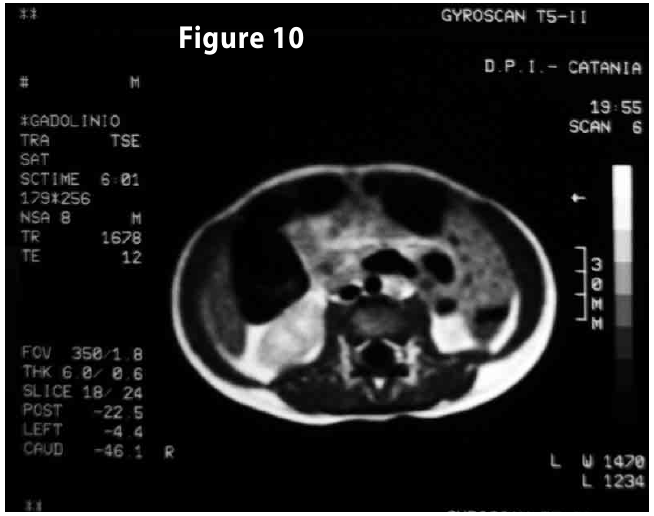

Figure10